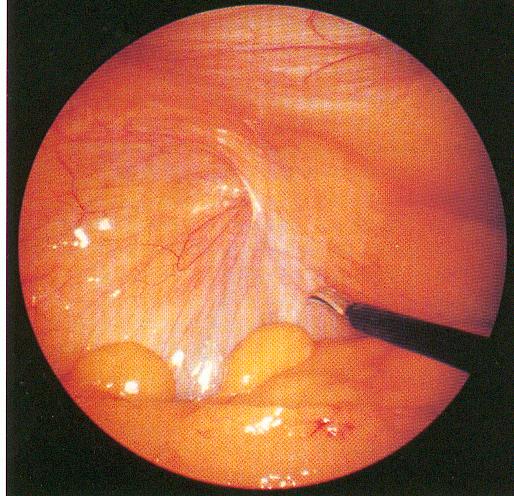

Βέβαια δεν πρέπει να ξεχνάμε ότι ναι μεν η μέθοδος της λαπαροσκόπησης είναι ο καλύτερη μέθοδος για την αντιμετώπιση ασθενειών και προβλημάτων, αλλά απαιτείται υψηλός βαθμός εκπαίδευσης και εμπειρίας από το χειρουργό που την εφαρμόζει δε.